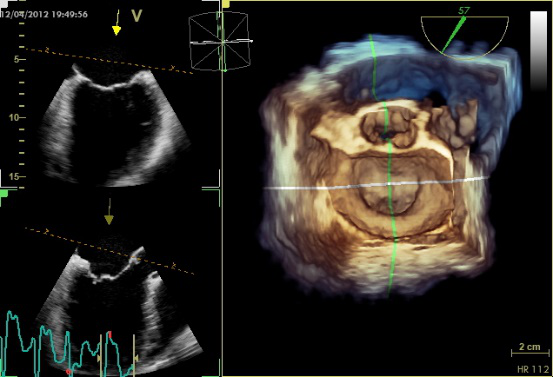

图10 TEE评价二尖瓣形态和功能的基本切面(标注二尖瓣分区)

TEE切面与二尖瓣分区的对应关系可用于二尖瓣脱垂部位的判断,但要注意的是:一定要将2D或3D图像与二尖瓣模型对应起来,不理解切面和模型之间的空间关系,直接用文献上的分区对应实际的超声图像会导致定位不准和交流障碍(图11,12,13,14);另外,经胃底基底段短轴切面对诊断瓣叶裂和穿孔很有帮助,彩色多普勒可以提供有关反流束起源的信息(图14)。

图11四腔心切面显示二尖瓣后叶P2区脱垂

图14经胃底基底段短轴切面。示二尖瓣前后叶,P3区位于“扇形”的顶点